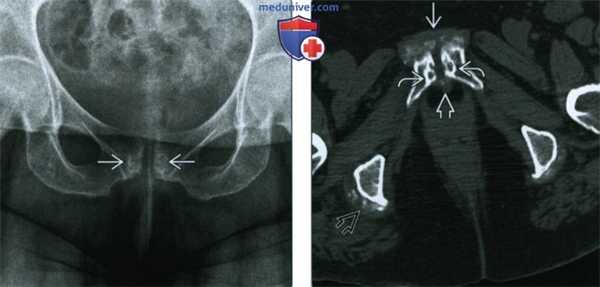

(Слева) КТ, костное окно, аксиальный срез: в подвздошной мышце определяется мягкотканное объемное образование. В центре визуализируется аморфная область с плотностью кальцификата. Другие аномалии на этом изображении не наблюдаются.

(Справа) КТ, костное окно, аксиальный срез: изображение, полученное при исследовании того же пациента шесть недель назад, через две недели после перенесенной травмы, приведшей к параплегии. Наблюдается нормальная картина. С учетом времени между нормальной картиной и появлением объемного образования с кальцификацией (шесть недель), эти изменения являются диагностическим признаком незрелого гетеротопического костного образования у пациента в группе риска, обусловленного параплегией. (Слева) КТ, аксиальный срез: томограмма полученная при исследовании этого же пациента через две недели после травмы. В объемных образованиях левой поясничной мышцы и запирательных мышц с двух сторон визуализируются аморфные кальцификаты.

(Справа) КТ, аксиальный срез: аномалии мышц не определяются. Визуализируются установленные этому пациенту со свежей параплегией ректальный зонд и катетер в мочевом пузыре. Наличие множества аномалий шесть недель спустя и наличие такого фактора риска, как параплегия, позволяет установить диагноз гетеротопического окостенения.